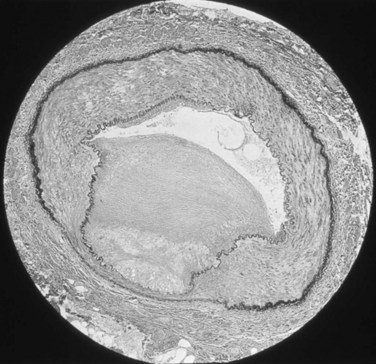

Approximately 70% of all renovascular lesions are caused by atherosclerosis (Novick et al, 1996). This disease may be limited to the renal artery but more commonly is a manifestation of generalized atherosclerosis, involving the abdominal aorta and coronary, cerebral, and lower extremity vessels. Atherosclerotic stenosis usually occurs in the proximal 2 cm of the renal artery, and distal arterial or branch involvement is distinctly uncommon. Owing to the proximal location of these lesions, oblique aortic views are often needed to adequately visualize the area of stenosis. The lesion involves the intima of the artery and, in two thirds of the cases, presents as an eccentric plaque (Fig. 39–1); in the remainder, the vessel is circumferentially involved, with narrowing of the lumen and destruction of the intima. Dissecting hematomas frequently complicate this disease, sometimes resulting in thrombosis of the entire vessel.

Figure 39–1 Histopathologic appearance of eccentric atherosclerotic plaque causing renal artery stenosis.